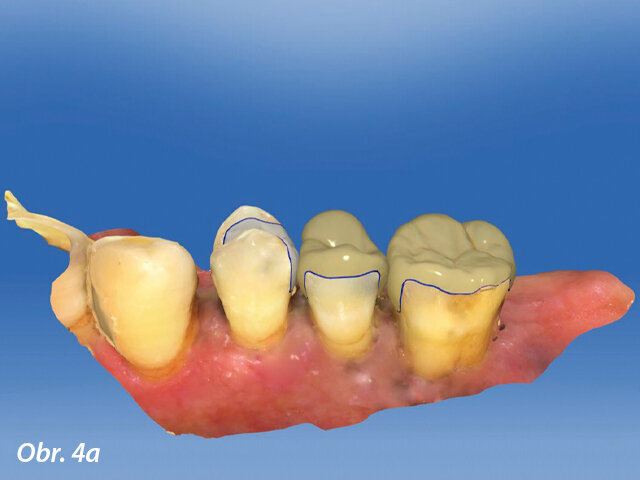

CAD výroba v dolní čelisti.